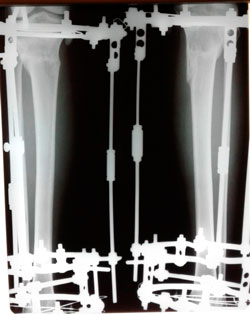

Исходник - 42 года.

Дата операции - 04.06.2020

в процессе работы